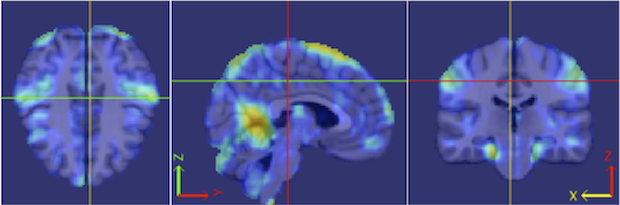

Our procedure is as follows. Each fMRI scan was separated into left and right hemispheres. Thus, each hemisphere contained voxels. Similar to standard group ICA (Calhoun et al., 2001b), a dimension reduction using PCA was applied to each hemisphere of each subject. 15 PCs are obtained for each hemisphere. A group data matrix was generated by concatenating the reduced data of both hemispheres of the 20 subjects in the temporal domain. Thus, the aggregated matrix has dimension , where , , and . Our algorithm of homotopic group ICA is then applied on this matrix. Fifteen estimated independent components are postulated by H-gICA. As shown in Figure 12, out of the 15 components, several brain networks were found including: the visual network 12, the default mode network 12, the auditory network 12, and the motor network 12. Compared with the ICs obtained from ordinary gICA, shown in 12, 12, 12 and 12, H-gICA improves the estimation of all of these sources by yielding substantially more clearly delineated networks.